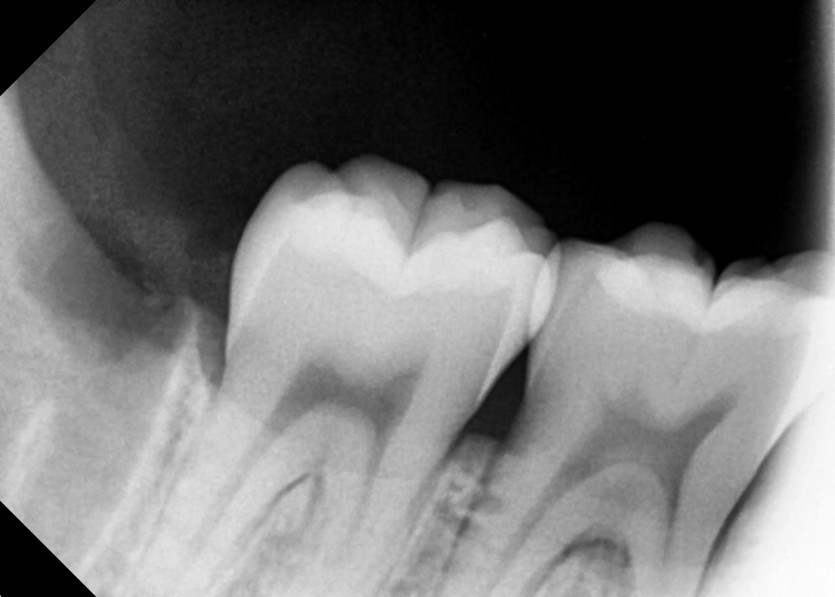

#18,48 사랑니 발치

구강 외과 전문의가 당일 발치했습니다.